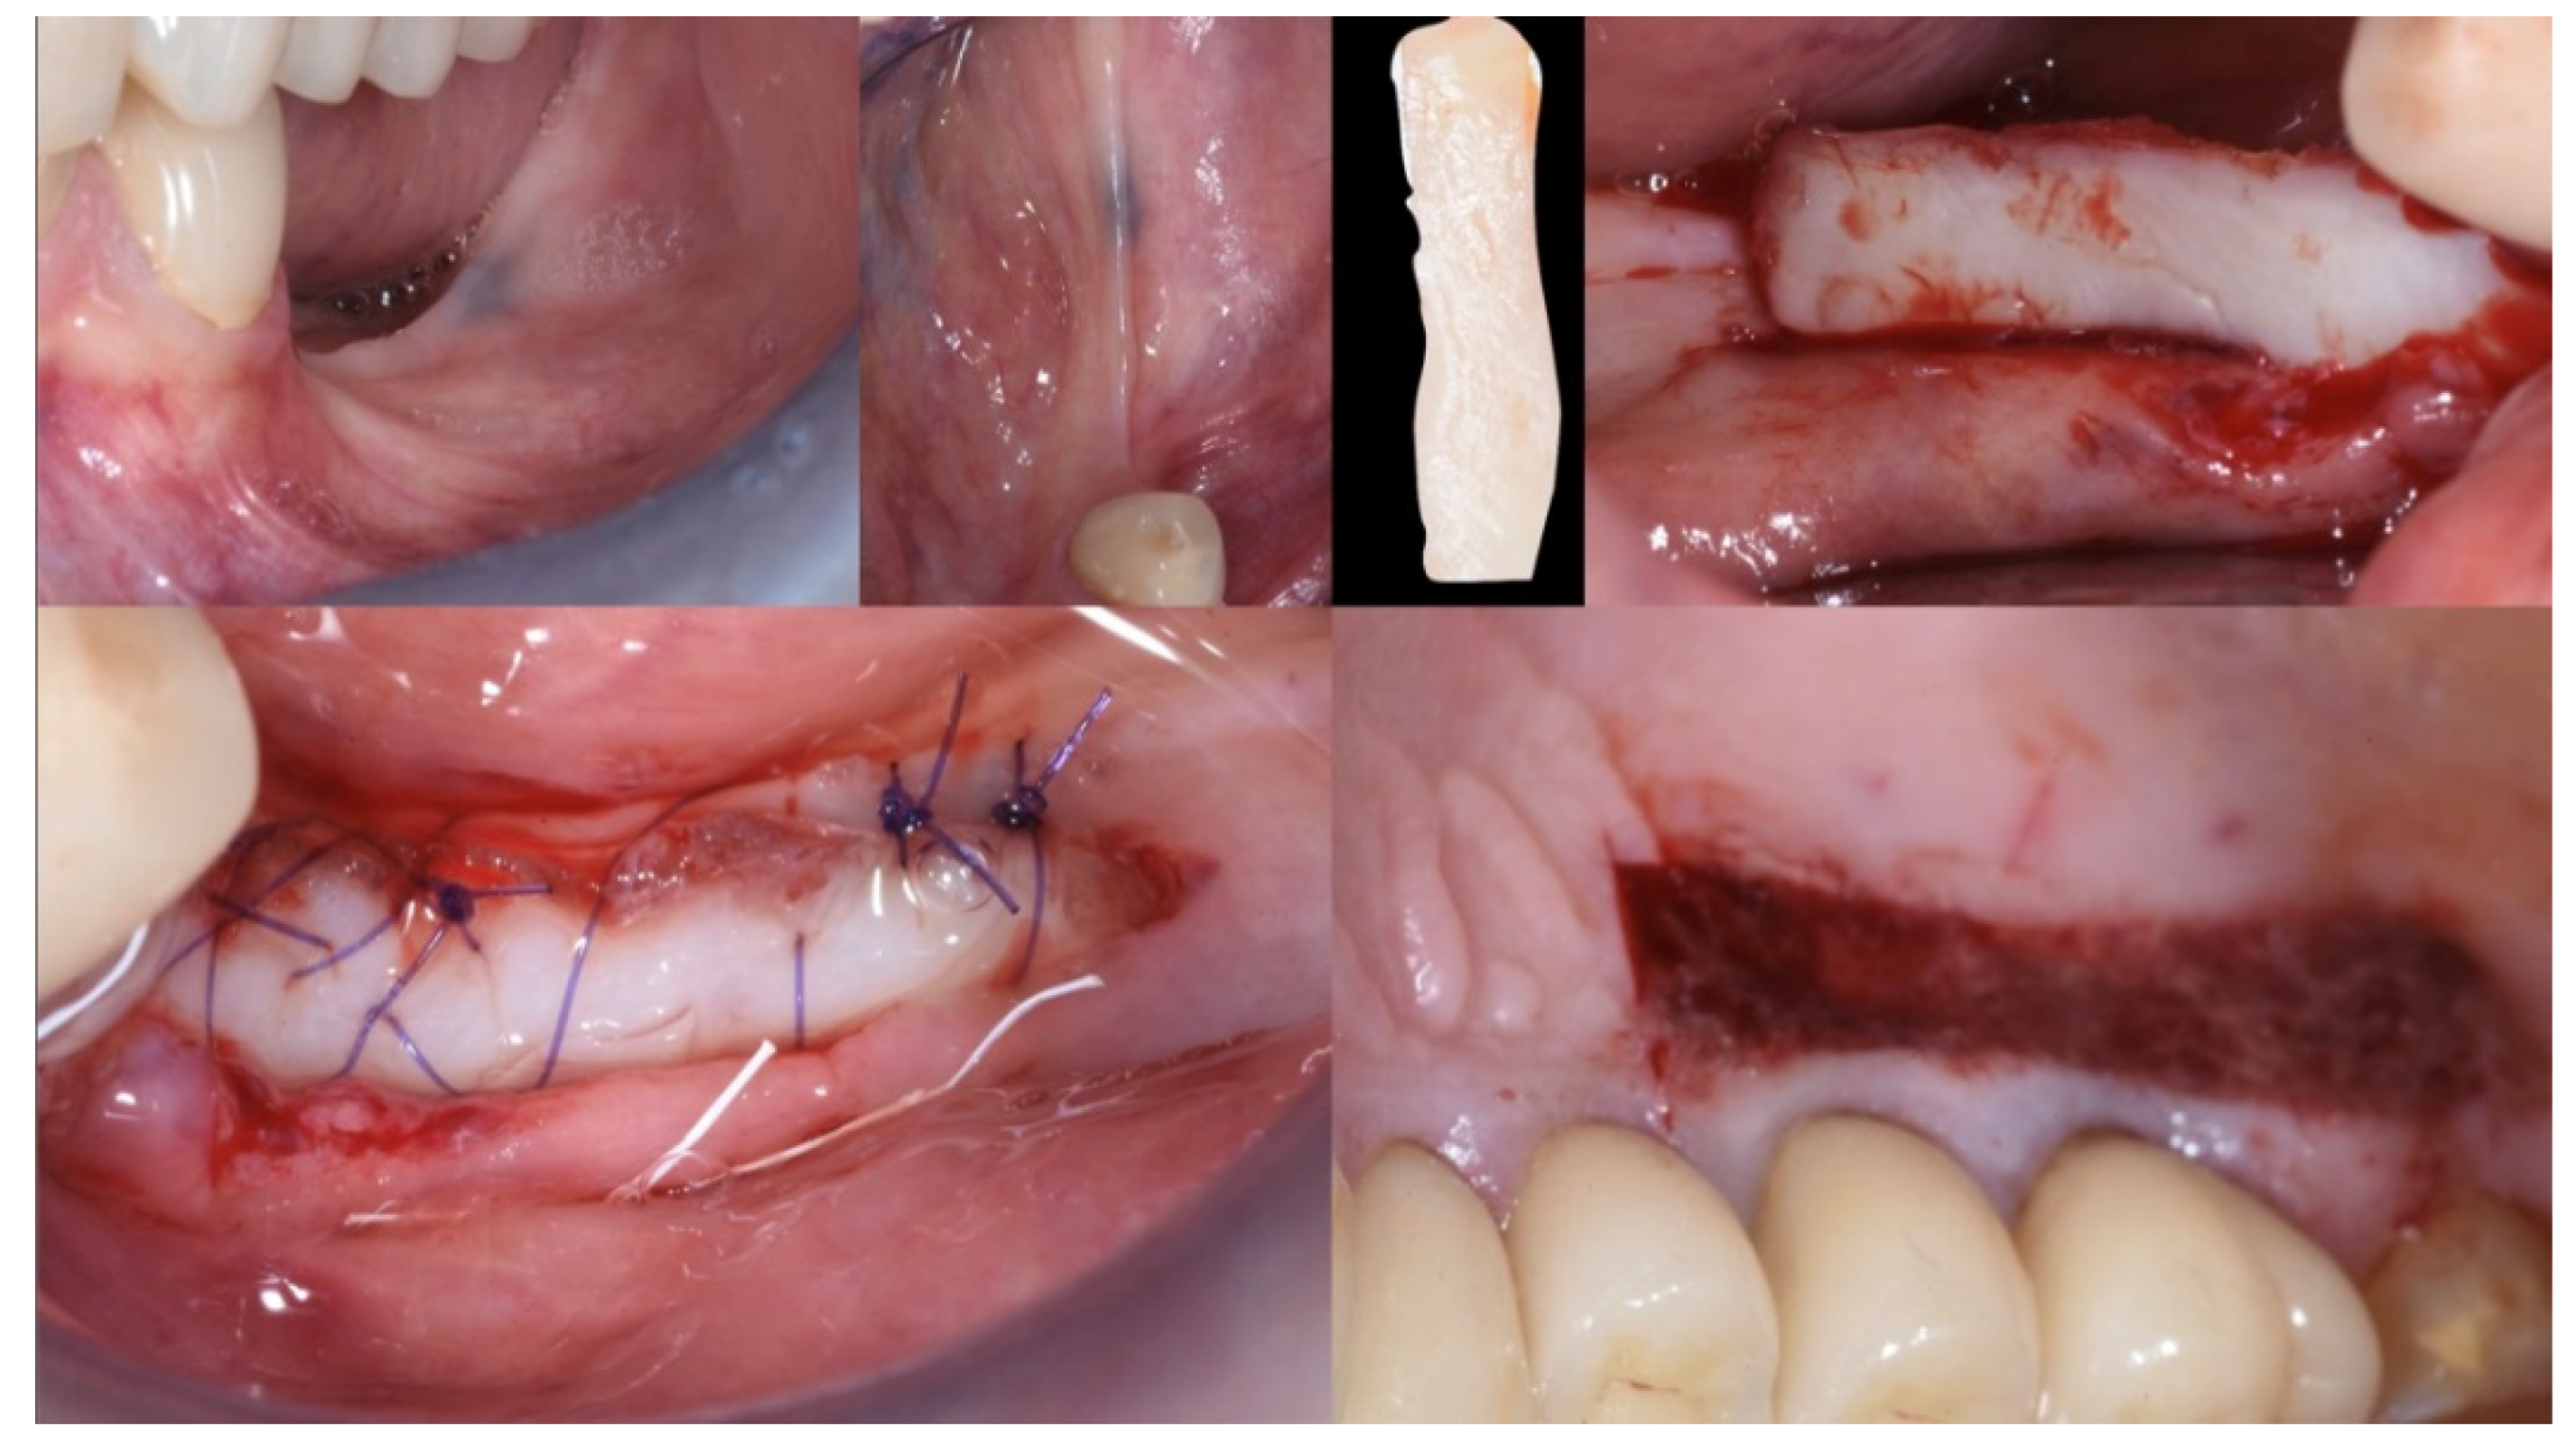

Local anesthesia (articaine 40 mg with adrenaline 1:200,000) was performed both in the donor and recipient sites. The recipient area was prepared with a split-thickness, apically positioned flap anchored to the periosteum with 5.0 PTFE sutures, leaving a bleeding recipient bed for the graft. The free gingival graft (25 mm × 6 mm) was harvested from the distal of the first bicuspid to the distal of the second upper molar. The donor area was protected with a few drops of octyl-butyl cyanoacrylate (Peri-Acryl® 90 HV, Osteophenix, Lecce, Italy). This material protects the wound and has a hemostatic effect. The free gingival graft was sutured at the recipient site with 5.0 polyglactin sutures (Flysorb®, Butterfly, Agrate Brianza, Italy) (Figure 4).

Figure 4.

Mucogingival surgery. A free gingival graft was used to enhance both the quality and quantity of the soft tissue of the edentulous ridge.

Three months after surgery, the graft showed a healthy color and optimal integration into the surrounding tissues. The mucogingival surgery provided good protection for the subsequent hard tissue regeneration (Figure 5).

Figure 5.

Soft tissue healing at three months.

Following local anesthesia (articaine 40 mg with adrenaline 1:200,000), a full-thickness flap was elevated both in the buccal and lingual aspects after a straight incision with a number 12 surgical scalpel. The atrophic ridge was then exposed to allow some autogenous collection from the lingual side. The harvested bone grafts were mixed with the blood clot, the collagenated xenograft, and the fibrin glue (Tisseel®, Baxter, Rome, Italy). The compound was applied as a small consecutive addition to the edentulous ridge, creating a completely new, much larger, and more stable ridge (Figure 6). Passivation of both buccal and lingual flaps was achieved through a soft brushing technique as described by Ronda and Stacchi [30], a very atraumatic way to coronally advance the soft tissue to protect the new volume.

Figure 6.

Guided Bone Regeneration. Flex Cortical Sheet (FCS) was positioned to cover the bone grafts.

The FCS sheet (Osteoxenon®, Flex Cortical Sheet, Bioteck SpA, Arcugnano, Italy) was shaped and trimmed to match the dimension of the regenerated area. The FCS was first tried in place and then glued in its final position to cover the grafts. The final width of the regenerated surgical site was 10 mm (Figure 5).

The mesial and distal papillae of the last tooth in the augmentation area were closed with a double sling 4.0 polyglactin suture (Flysorb®, Butterfly, Agrate Brianza, Italy) [29,31]. One or two horizontal mattresses were placed in the middle of the ridge to put pressure sideways on the new ridge and coronally advance soft tissue. The last is usually a continuous locking mattress, but even a single interrupted suture could work fine.

The final assessment showed both vertical and horizontal gains immediately after the surgical procedure (Figure 7). The profile of the atrophic ridge has turned from concave to convex.

Figure 7.

Comparison between the edentulous ridge before the surgery and immediately after the bone augmentation procedure.